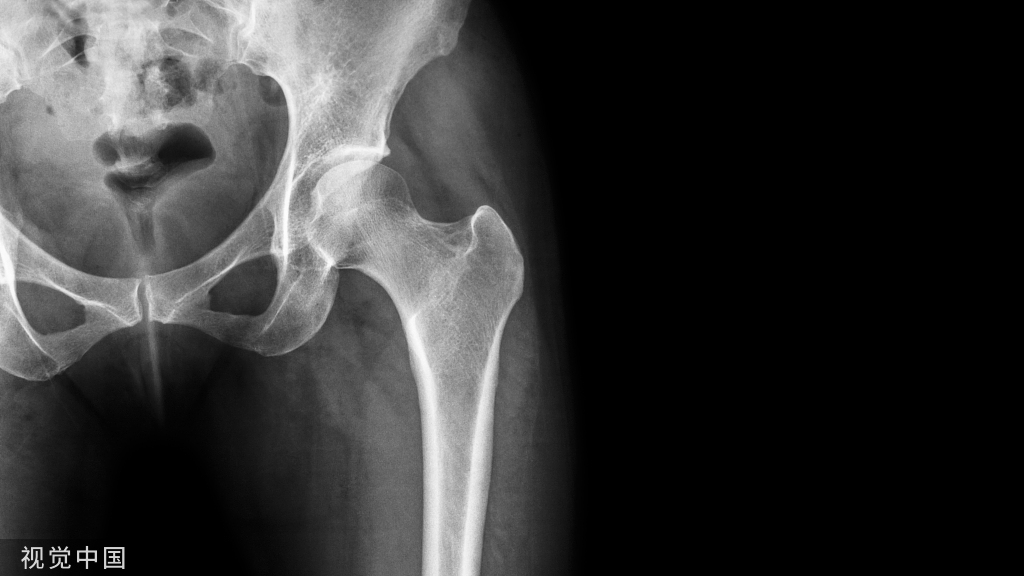

1、进钉点。髓内钉的位置在哪里最合适?

当然是髓腔的最中心,所以髓腔最中心的延长线就是最佳的进钉点。一般位于梨状窝。一个好的进针点可以保证力线,同时进钉后还有复位的作用,如果进钉点出现了偏移,可能整个手术都会有影响。好的开始象征着接下来手术的顺利,一定要取一个好的进针点。

他在正侧位的透视位置我们可以看到位于髓腔中心的延长线上

随着有外翻角的髓内钉的发明,我们现在目前用的可能多是大粗隆顶点进针的了

进针的角度,基本与股骨颈是垂直的角度

我们在做粗隆间骨折的时候由于骨折线经常经过进针点而出现近端内移的情况

注意采用快钻慢进,用套筒来纠正方向。